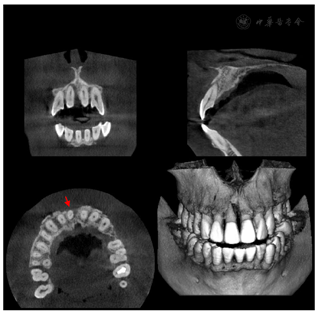

11牙冠完整,扣(-),Ⅰ度松动,唇侧牙龈约牙根中部位置膨隆呈半球型,唇侧牙周袋溢脓,唇侧近中及中央位点PD> 10 mm,余位点PD 2~3 mm。X线根尖片示:11近中牙槽骨环绕牙根牙周病样角型吸收达根尖,远中牙槽骨未见明显异常,见图1。CBCT示:11唇侧近中牙槽骨环绕牙根缺损自冠方达根尖,根中段疑似根折影像,见图2。